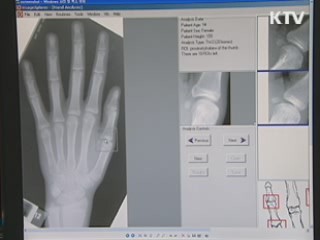

성조숙증 진단을 받은 10세 여아의 X-Ray 사진입니다.

손가락 마디 사이에 있어야 할 성장판이 보이지 않고 뼈와 뼈가 맞닿아...